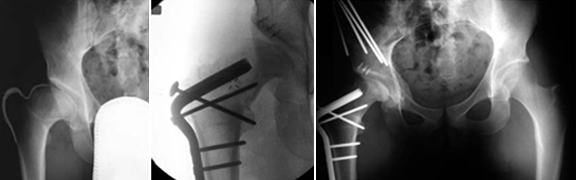

O que aconteceu na epifisiólise foi um descolamento pela zona da cartilagem de crescimento, com o subsequente deslizamento da cabeça para baixo e para trás (para posteroinferior) em relação ao colo femoral.

O estudo imagiológico é feito com Rx e se necessário a TAC.

O doente sintomático é candidato a cirurgia conservadora da anca e é efectuado tratamento cirúrgico que consiste em recolocar a cabeça femoral em posição o mais anatómica possível, e com a técnica cirúrgica da “luxação segura”.